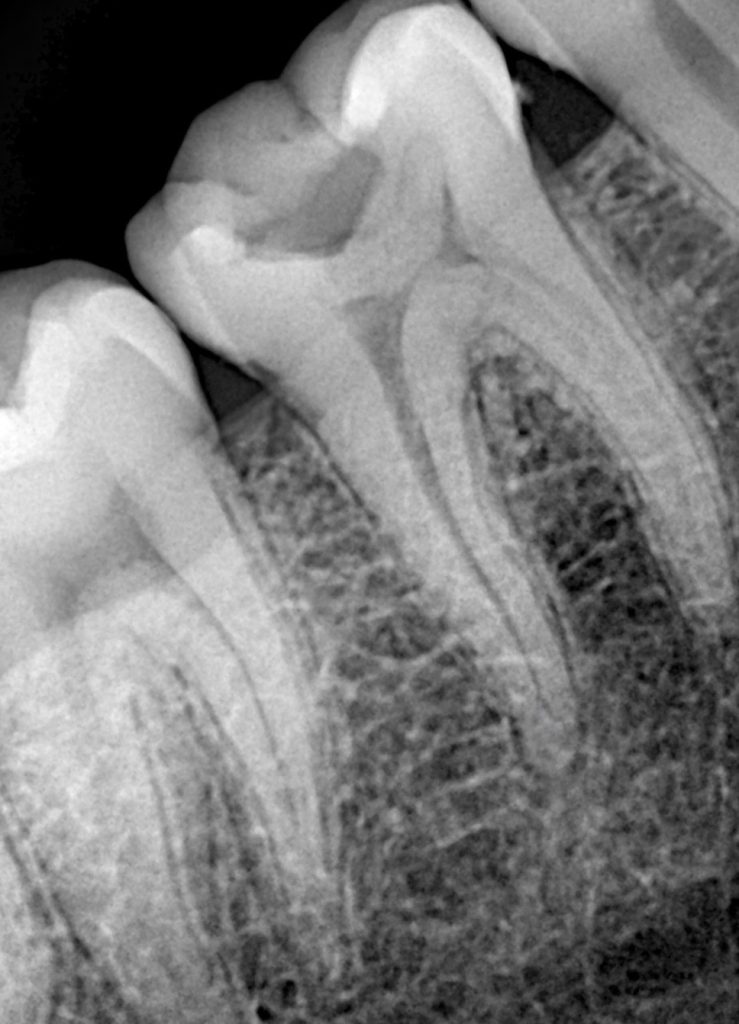

Canals were negotiated and working length was established using radiographic verification. Shaping was carried out with a controlled, minimally invasive approach to maintain canal anatomy while allowing effective irrigation and disinfection.

Obturation Using Warm Vertical Compaction

Following thorough cleaning and drying, obturation was completed using warm vertical compaction. Thermoplasticized gutta-percha allowed for intimate adaptation to canal walls, isthmuses, and apical complexities, providing a dense, homogeneous three-dimensional seal. Post-obturation assessment confirmed appropriate length control and obturation density.

The final restoration demonstrated proper occlusal form, functional harmony, and a secure coronal seal. Radiographic evaluation confirmed stable obturation without signs of periapical pathology. By integrating endodontic and restorative phases into a single biologically driven workflow, the tooth was returned to function with an optimized long-term prognosis.